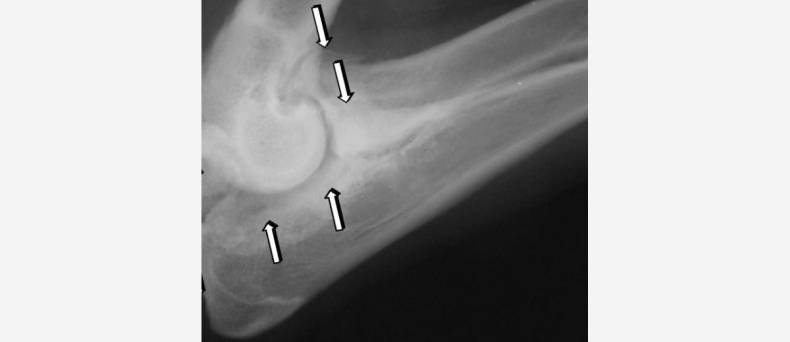

Naast het nemen van een röntgenfoto van de aangedane poot van de hond wordt de diagnose van osteosarcoom gesteld op basis van de verschijnselen en bevindingen bij het lichamelijk onderzoek en het onderzoek van het bewegingsapparaat.

Bron foto: Joel Mills, Canine osteosarcoma, resized, cropped, CC BY-SA 3.0